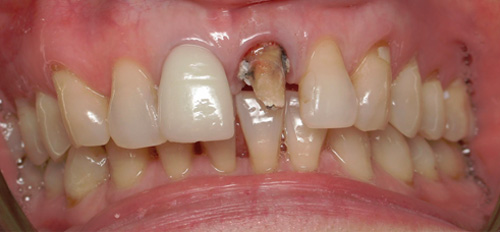

Smile Gallery

Orthodontic Treatment X-ray - Before

After Series of Teeth Extractions, Upper Left Canine Unerupted.

Ready to Start Ortho Treatment